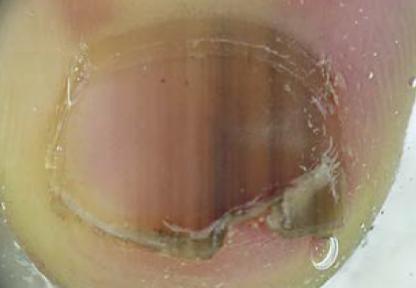

2、 指甲上有横线:

博氏线(Beau's line)是小儿常见的指甲横线。

可以看到指甲出现横贯指甲的凹痕,凹痕远端的指甲有有剥离、脱落、断裂的现象。

1、此类情况常见于手足口病恢复期,多发生在疾病康复后1-2个月;

2、极少数的猩红热、川崎病、化脓性扁桃体炎等感染后也可造成这种情况;

3、造成这种情况的主要原因,是因为病毒复制损害了甲基的生长,使甲生长时间停滞,从而导致横脱落、横断的发生;

4、此类情况无需特殊处理,可自行恢复,但须注意保证手部卫生,不要受伤。